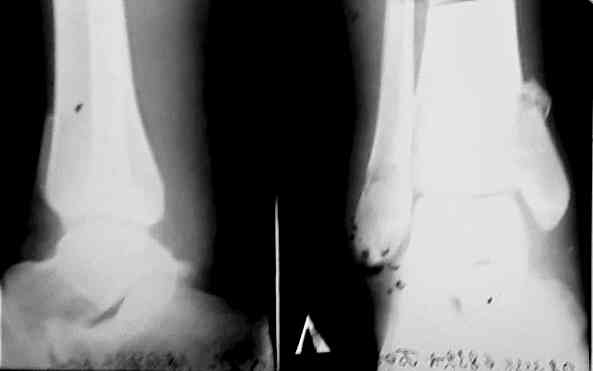

Доброго времени суток,коллеги! Вчера обратился на консультацию 22-летний больной. Травма 26.09.06. 30.09.06 оперирован. 30.11.06 Гипс снят снимки после снятия гипса представляю.

Качественные снимки постараюсь прислать через неделю

Как говорил мой шеф - снимки корзиночные (в смысле в корзину) - трудно советовать что либо. Сделайте свеже-хорошие пли-и-з. А пока пусть восстанавливает локомоцию в суставе - это не во вред.